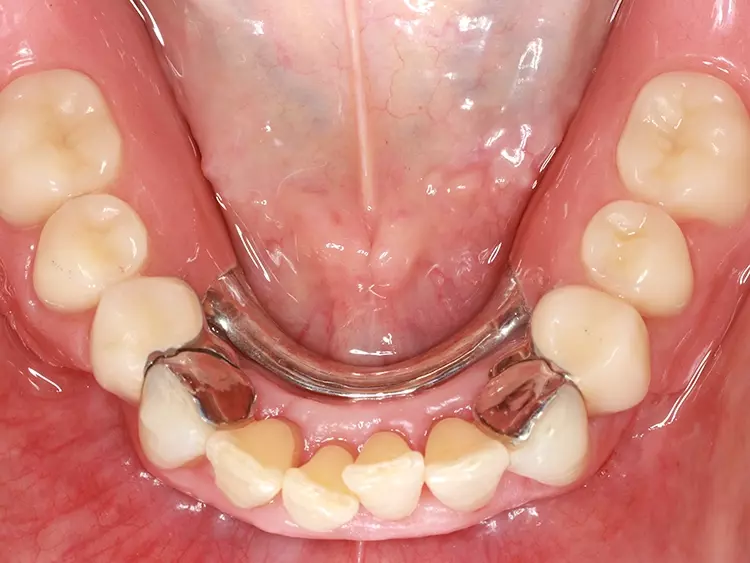

Als relative Kontraindikation sind karies- und restaurationsfreie Pfeilerzähne mit zervikalen keilförmigen Defekten über 1 mm Tiefe zu nennen, da diese zu einer erhöhten Frakturgefahr des Pfeilerzahnes bei Belastung führen. Adhäsivattachments können zur Reparatur vorhandener Doppelkronen- oder Geschiebearbeiten verwendet werden, sofern der verbliebene Nachbarzahn einer verloren gegangenen Doppelkrone karies- und restaurationsfrei ist. Die Matrize wird in diesem Fall in die ausgeschliffene Doppelkrone oder in die Geschiebekrone des verlorenen Pfeilerzahns eingeklebt (Abb. 1 bis 4).